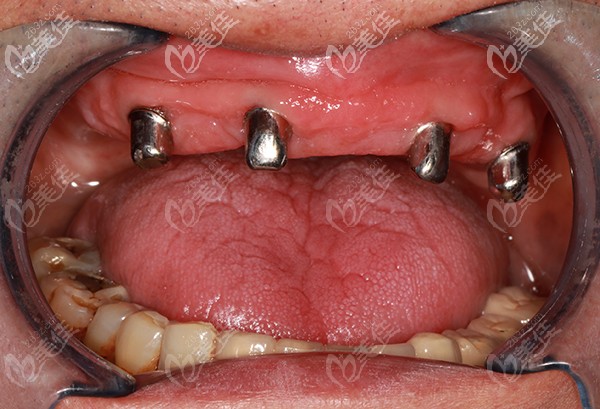

种植牙植入后

种植后口内检查照片

半口种植不需要为每一颗牙齿都植入种植体,我爸做的是allon4,也就是只需要4颗种植体的种植牙技术,便可以进行半口牙(12-14颗牙齿)的种植。